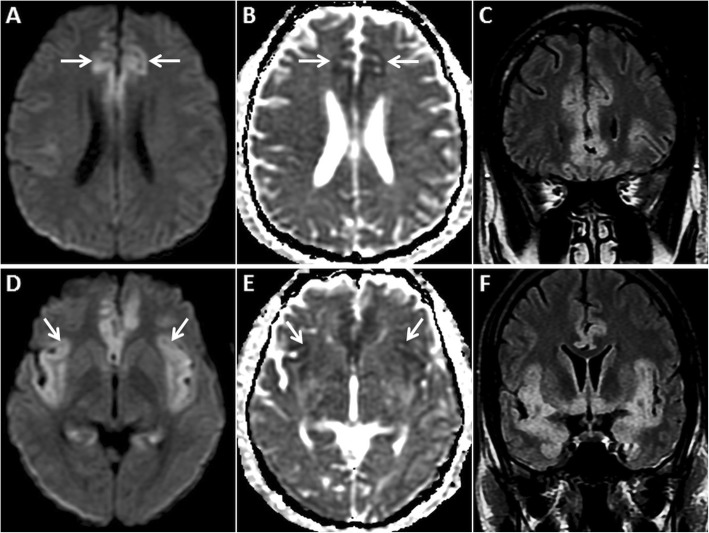

Fig. 9.

MRI of the brain in a 58-year-old female patient who presented with rapidly progressive dementia due to sCJD. Symmetric GRD is seen in the cerebral cortices on axial DWI (a, d) and ADC images (b, d, e) with sparing of the perirolandic regions (asterisks in a, b). Coronal FLAIR images (c, f) shows hyperintense signal in the affected cortices

Fig. 10.

Pre- and post-contrast MRI of the brain in a 55-year-old male patient who presented with rapidly progressive dementia due to sCJD. GRD is seen in the left temporo-parieto-occipital region (arrows) and in the insular regions on axial DWI (a) and ADC image (b). Nearly symmetric restricted diffusion is also seen in the basal ganglia (dashed arrows) along with mild DWI hyperintensity in the pulvinar nuclei (arrowheads). Axial T2W image (c) shows T2 hyperintensity in the basal ganglia (dashed arrows) and pulvinar nuclei (arrowheads). Sequential anteroposterior FLAIR images (d, e) demonstrate the extent of the cortical signal abnormality (arrows). No enhancement is seen in these regions on axial post-contrast T1W image (f)

Fig. 11.

Pre- and post-contrast MRI of the brain in a 45-year-old male patient with proven MELAS on muscle biopsy. GRD is observed in the right parietal cortex (arrows) on axial DWI (a) and ADC image (b). Associated gyral swelling and hyperintense signal (arrows) is seen on axial T2W (c) and coronal FLAIR image (d). No enhancement is seen in this region on post-contrast axial T1W image (e). Reconstructed maximum intensity projection MRA image of Circle of Willis (f) confirms no large vessel occlusion